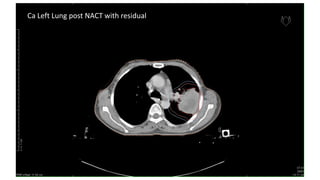

Ca Left Lung post NACT with residual

Ca Left Lungpost NACT with residual

For patients who have undergone induction

chemotherapy with a reduction in tumor size

• Parenchymal lesions:

➢Target post-chemotherapeutic volume with GTV

➢Coverage of pre-chemotherapeutic volume with CTV

• Involved lymph nodes:

➢Post-chemotherapy volume covered with GTV

➢Entire nodal station (superior-inferior extent) covered with CTV.